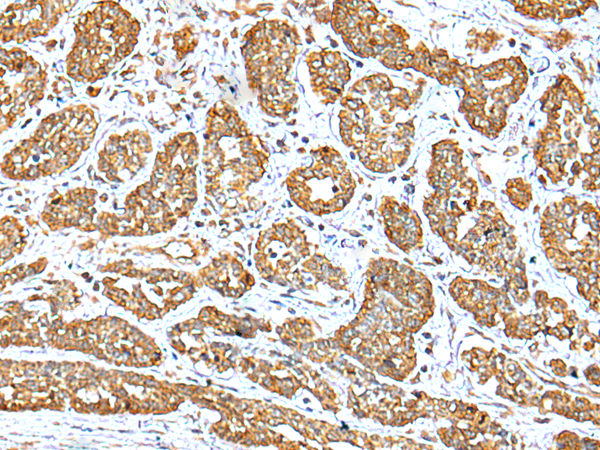

IHC positive control: |

Human breast cancer and human esophagus cancer |

IHC Recommend dilution: |

25-100 |